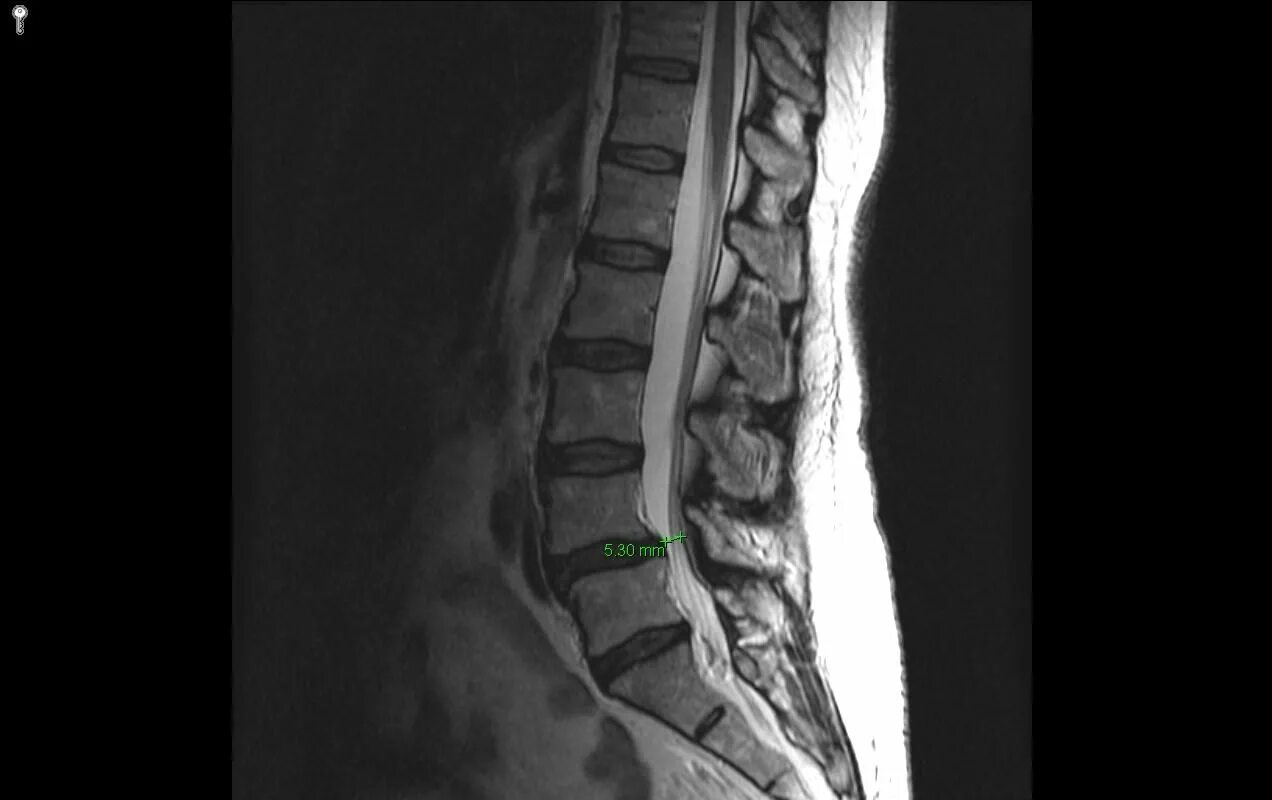

Чем отличается кт от мрт поясничного отдела